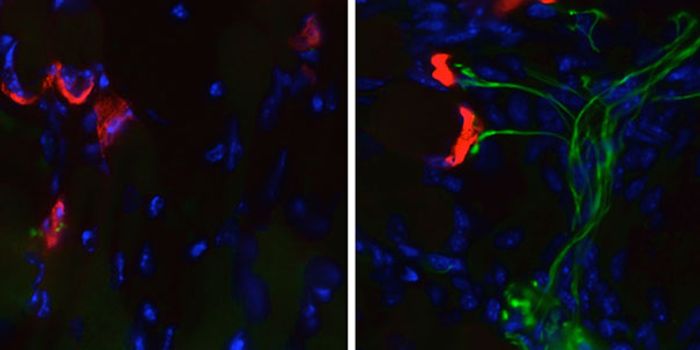

MAR 03, 2016Cell & Molecular BiologyFor the first time, scientists have turned skin cells into cancer-hunting stem cells that destroy brain tumors known as ...